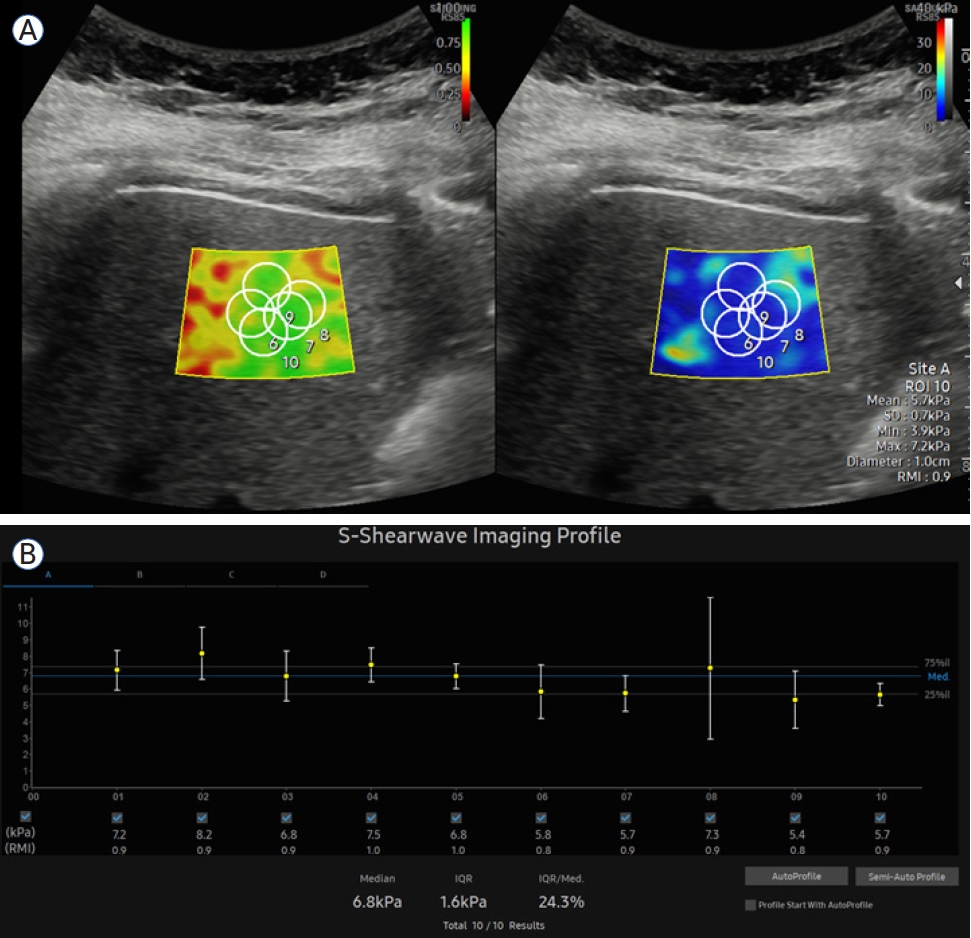

SWE는 크게 point SWE (pSWE)와 2D-SWE로 분류된다[1]. pSWE는 acoustic radiation force impulse (ARFI)를 이용하여 탐촉자에서 좁은 영역에 초점을 맞춰 음파를 발생시킨 후 관심 영역(region of interest, ROI)에 도달하는 횡파의 속도를 측정하는 기법이다. 측정 영역이 상대적으로 작지만 검사 장비가 비교적 간단하고 ROI 설정이 용이하며 반복 측정이 가능하다는 장점이 있다. 반면 2D-SWE는 pSWE와 달리 여러 초점에서 연속적으로 음파를 발생시켜 원뿔 모양으로 확산되는 횡파를 측정하여 더 넓은 범위의 탄성도를 동시에 분석할 수 있다. 이를 통해 2차원 영상에서 간실질 내 탄성 분포를 컬러 맵으로 시각화할 수 있으므로 보다 직관적으로 간의 국소적 섬유화 정도를 파악할 수 있다는 이점이 있다(Fig. 1). 특히 2D-SWE는 다양한 장비 회사와 기법에 따라 cut-off value 범위가 다소 넓게 보고되기도 하지만 전반적으로 pSWE와 유사하거나 더 나은 민감도 및 특이도를 제시하고 있어 실제 임상에서 간편하고 효과적인 방법으로 자리매김하고 있다.

Figure 1.

2D-shear wave elastography examination example. (A) A region of interest is set approximately 1.5 cm below the liver surface. The left screen displays the measurement quality, indicated by colors ranging from red to green, representing low to high measurement quality. Measurements are taken 5-10 times within the green area. The right screen shows liver stiffness, indicated by colors ranging from blue to red, representing low to high liver stiffness. (B) The median of the measured values is taken as the final result, and reliability is considered high if the interquartile range divided by the median is less than 30%.